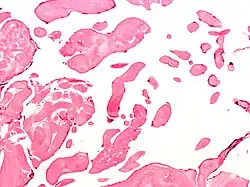

Micrograph of an excised aortic valve papillary fibroelastoma showing that the avascular branching papillae are covered by endothelium. H&E stain.

Papillary fibroelastoma are typically found and accurately diagnosed by imaging. The diagnosis is confirmed by pathology. Histologically, papillary fibroelastomas have branching avascular papillae, composed of collagen, that are covered by endothelium.